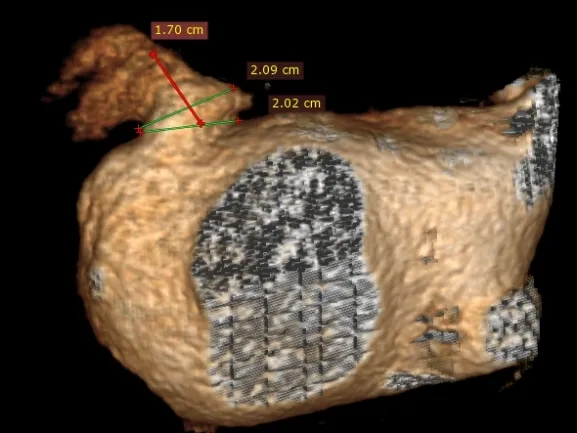

术前检查:心脏CT三维重建确认开口直径与心耳深度

RAO30度

CAU20度

左心耳大小20.1*17mm

CT三维平面左心耳开口形态及大小

左心耳开口近圆形,MPR周长66.4mm,化圆直径21.1mm,预选LAFDQ-23封堵器进行封堵

左心耳开口偏小,术前CT三维重建测量工作位左心耳大小20.1*17mm,正足位20度左心耳大小20.3*15.5mm,术中肝位造影确认左心耳大小为23.5*18.1mm。